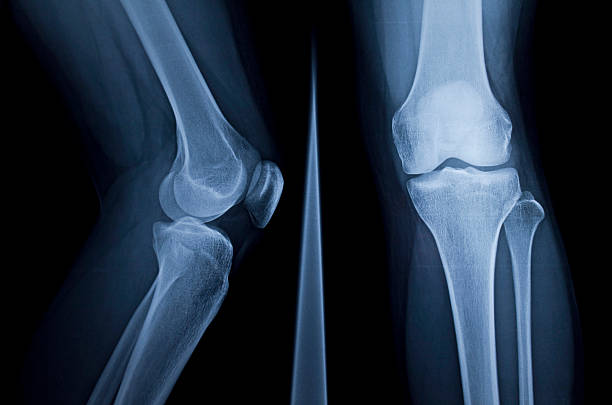

무릎 연골 손상 증상은 이미 연골이 찢어지고 부러진 경우 통증이 너무 크기 때문에 무릎을 구부리거나 펴거나 제대로 기능하지 못하는 경우가 돼서야 인식하는 경우가 많습니다. 이 경우 연골에 염증이 생기고 증상이 너무 심해 병원에 가서 진찰을 받아야하며 정확한 검사 없이는 정확한 진단이 불가능하고 적절한 치료를 받을 수 없기 때문에 준비를 잘 하셔야 합니다.